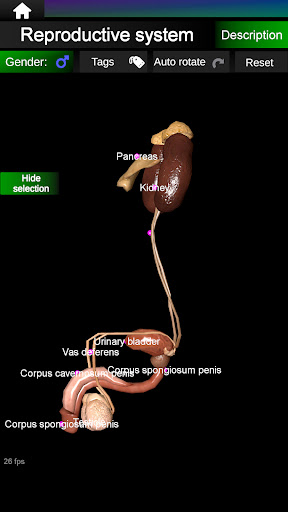

* Репродуктивна система, яка включає чоловічі та жіночі репродуктивні органи.

* Порівняйте чоловічі та жіночі органи.